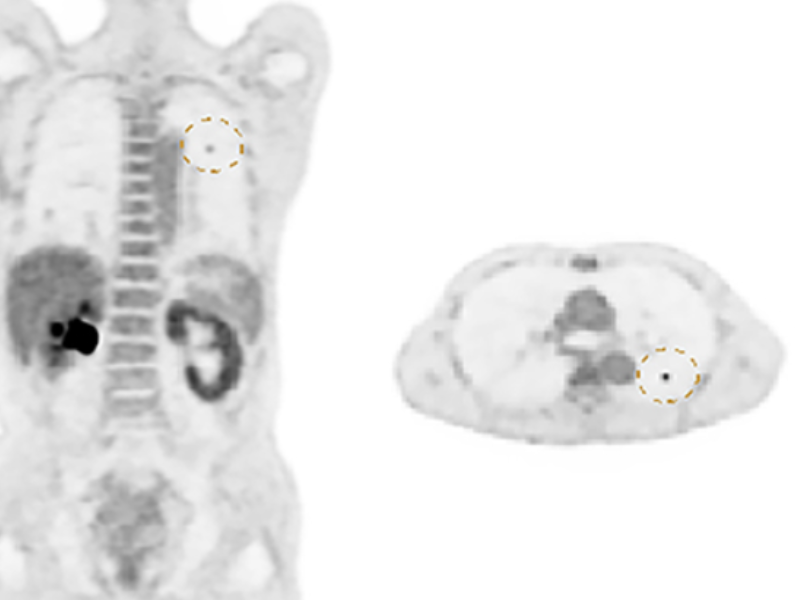

Lesion Detectability for PET